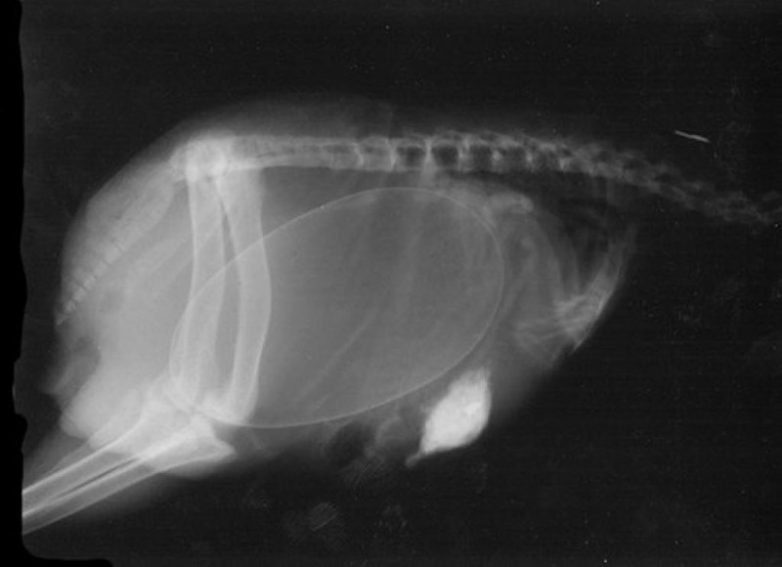

Беременные животные под рентгеном

Так выглядят рентгеновские и ультразвуковые снимки беременных животных.

Беременная птица киви